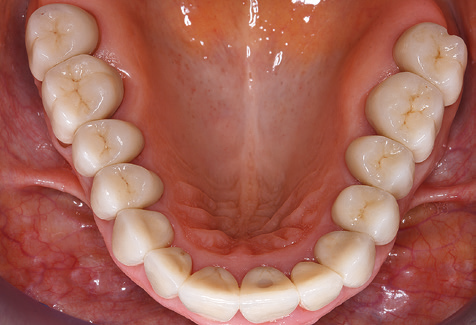

Fig. 9: The accessible implant and tooth surfaces are polished with polishing cups and suitable polishing compounds. – Fig. 10: Repeat instruction in the use of appropriate aids for oral hygiene at home should also form part of SPT. – Fig. 11a and b: Clinical situation 12 years after insertion of the prosthetic restoration. During this period, only a veneering ceramic fracture on tooth 47 and the requirement for endodontic treatment of tooth 12 were observed. All restorations are still functioning as intended.

Standardised and regular risk-adapted care in the scope of SPT is the key to treatment success for the clinical long-term success in periodontically compromised patients. This is particularly true for patients fitted with implants following successfully completed periodontal treatment (Fig. 11a and b).